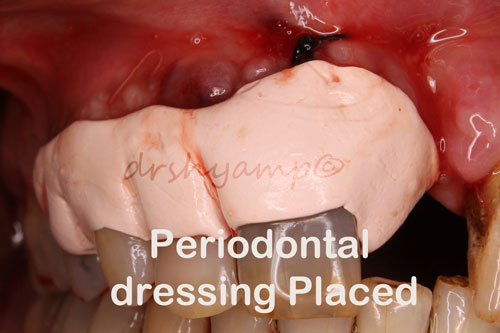

Periodontal flap surgery with bone grafting

Periodontal flap surgery with bone grafting

Periodontal flap surgery with bone grafting

Periodontal flap surgery with bone grafting

Periodontal flap surgery with bone grafting

Periodontal flap surgery with bone grafting

Periodontal flap surgery with bone grafting

Periodontal flap surgery with bone grafting

Periodontal flap surgery with bone grafting

Periodontal flap surgery with bone grafting

Periodontal flap surgery with bone grafting

Periodontal flap surgery with bone grafting

Periodontal flap surgery with bone grafting